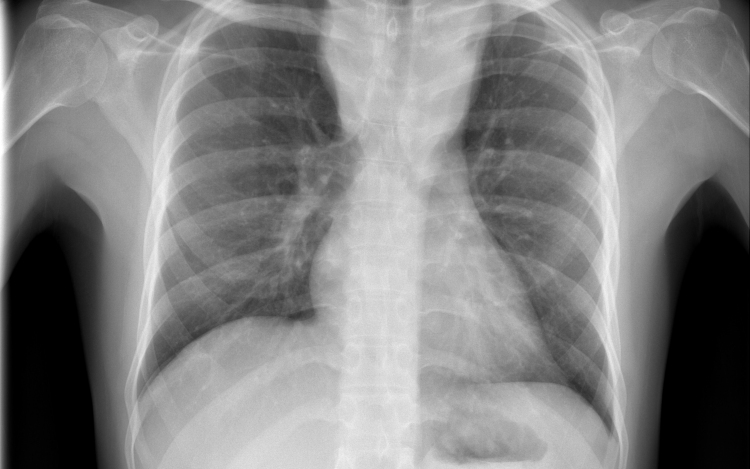

Hétfő reggel óta tbc-tesztet végeznek el a gyerekeken egy szatymazi általános iskolában, ahol egy hete fertőző tüdőbetegségben halt meg egy korábban ott dolgozó nő - közölték az M1 aktuális csatorna déli Híradójában.

A Délmagyar hírportál hétfő reggel írt arról, hogy februárig dolgozott a szatymazi iskolában közmunkásként az nő, aki tuberkulózisban (tbc) halt meg egy hete. Az ügyben rendkívüli szülői értekezletet tartottak. Az általános iskola 260 tanulója közül szülői beleegyezéssel 250-en végzik el a tbc-tesztet.

Az M1 tudósítója a helyszínről azt mondta: több szülővel beszéltek, ők nem voltak megriadva; elmondták, hogy az iskola azonnal tájékoztatta őket arról, mi történt a nővel, aki takarítóként dolgozott az iskolában február végéig. A tudósító megjegyezte, a tbc tüneteinek lappangási ideje 28-30 nap, ez az idő már letelt, de egyetlen gyereken sem tapasztaltak egyetlen tünetet sem.

Felidézték, hogy Magyarországon 1954 óta kötelező a tbc elleni védőoltás. Most az iskola diákjain biztonsági intézkedésként végzik el az úgynevezett Mantoux-tesztet, amely kimutatja, hogy védettek-e a tbc ellen. Ezt a tesztet később, három és hat nap múlva is megismétlik - hangzott el a Híradóban.